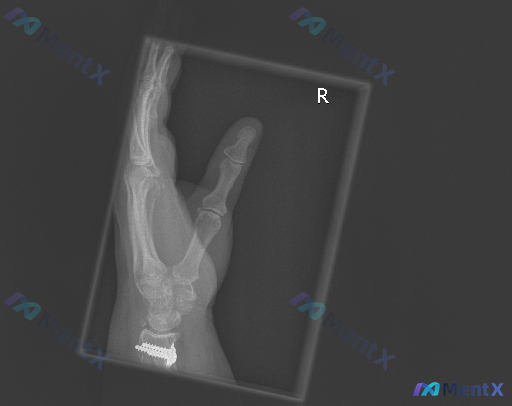

整理到一份右手斜位X线片的影像分析资料,觉得很适合拿出来讨论阅片思维。 先讲客观发现: - 投照是右手斜位,拇指和四指分开,但手指有重叠 - 最显眼的是腕关节区域有金属内固定(钢板+多枚螺钉),位置看起来还行,没看到明显断裂松动 - 第1-5掌骨、拇指近远节指骨,在可见范围内没看到明确的皮质中断或错...